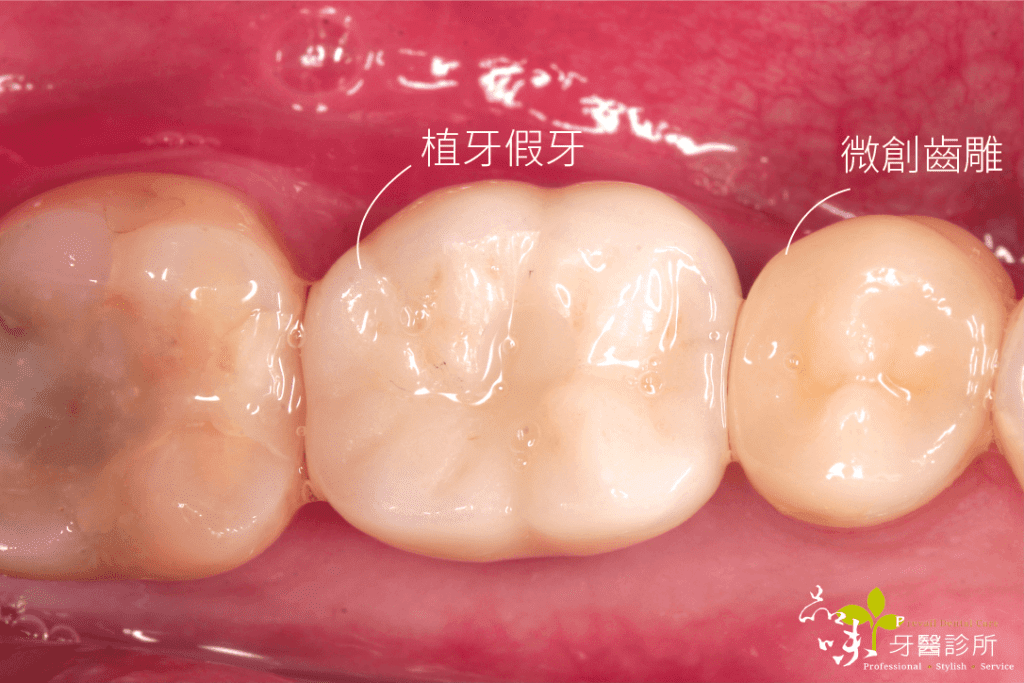

前牙美觀區的即拔即植術後,當下會裝戴臨時假牙,手術當天就有牙齒可以使用,之後一樣等 4 至 6 個月再裝上正式假牙。

- 重建後的外型較美觀(減少拔牙後骨頭與牙肉吸收量,牙齦恢復較飽滿,因此較容易達成外觀自然的植牙)

傷口在幾天後再也沒有疼痛感,後續回診追蹤也沒有不舒服。就這樣,四個月很快地過去了,假牙醫師幫他裝好全陶瓷的假牙。現在他可以開開心心地盡情享用美食。